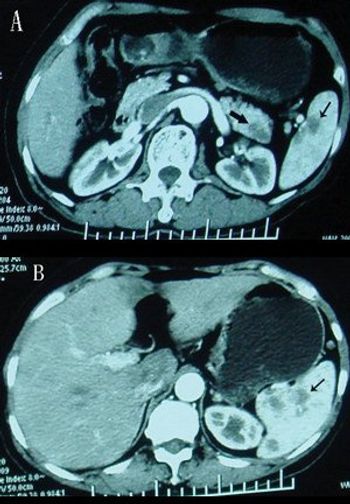

Developing a scoring system for staging patients with hepatic colorectal metastases is important for prognosis and for identifying those who will benefit from additional systemic therapy.

Due to advances in chemotherapy, biologic therapy, and the development of liver-oriented treatment options, the survival of patients with metastatic cancer has more than doubled, and increasing numbers of patients have been cured, even among those with advanced disease.

This article will review the current practice of hepatic resection for colorectal liver metastases, including the possibility of combined resection of hepatic metastases at the time of resection of the primary cancer.